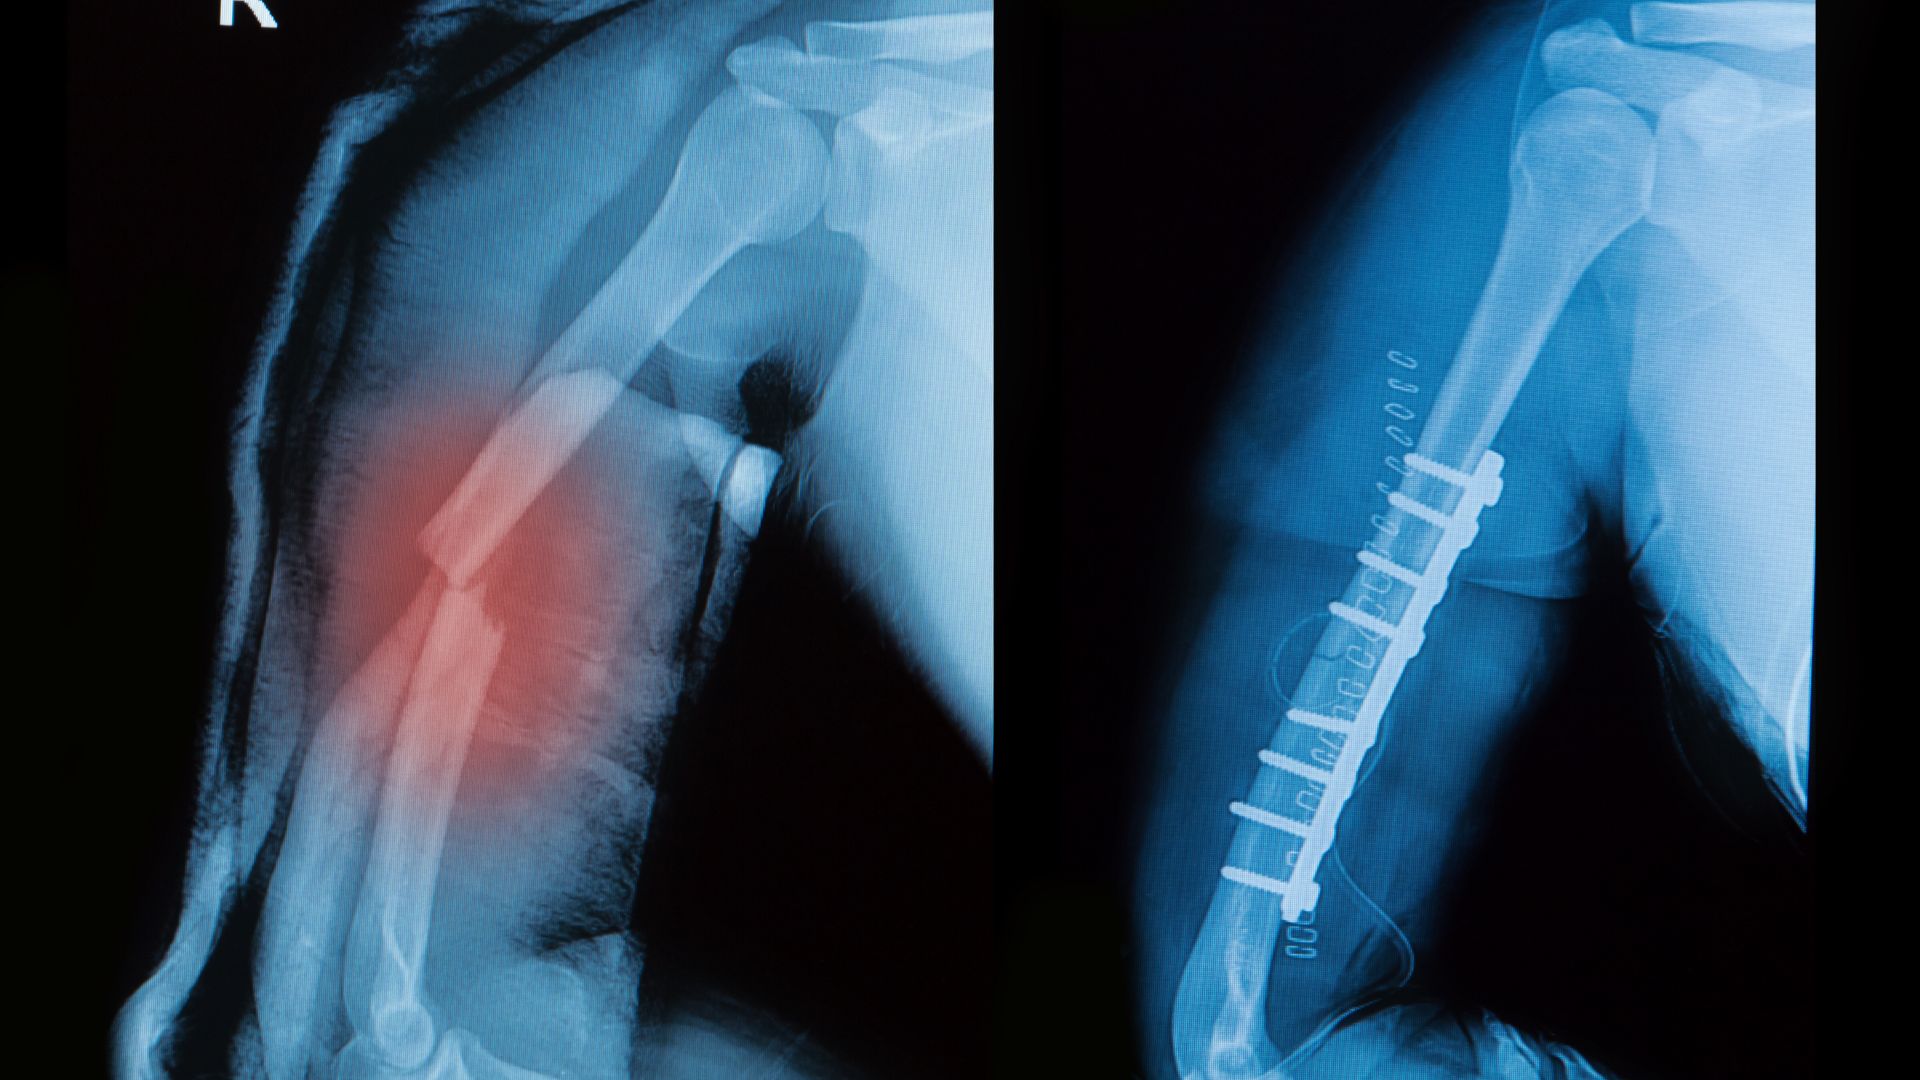

Phương pháp này thường được áp dụng cho các trường hợp gãy ít di lệch hoặc không di lệch. Sau khi đánh giá bằng hình ảnh như X-quang, CT… bác sĩ sẽ nắn chỉnh và cố định tay bằng bột hoặc nẹp trong thời gian phù hợp. Trong quá trình điều trị, người bệnh cần tái khám định kỳ để kiểm tra tình trạng liền xương và phát hiện sớm nguy cơ di lệch thứ phát.

Điều trị can thiệp chỉnh hình

Với những trường hợp gãy di lệch nhiều hoặc có dấu hiệu chèn ép mạch máu, thần kinh, bác sĩ có thể chỉ định can thiệp chỉnh hình. Sau can thiệp, việc chăm sóc, theo dõi và tuân thủ hướng dẫn phục hồi đóng vai trò quan trọng trong việc đảm bảo kết quả điều trị lâu dài.